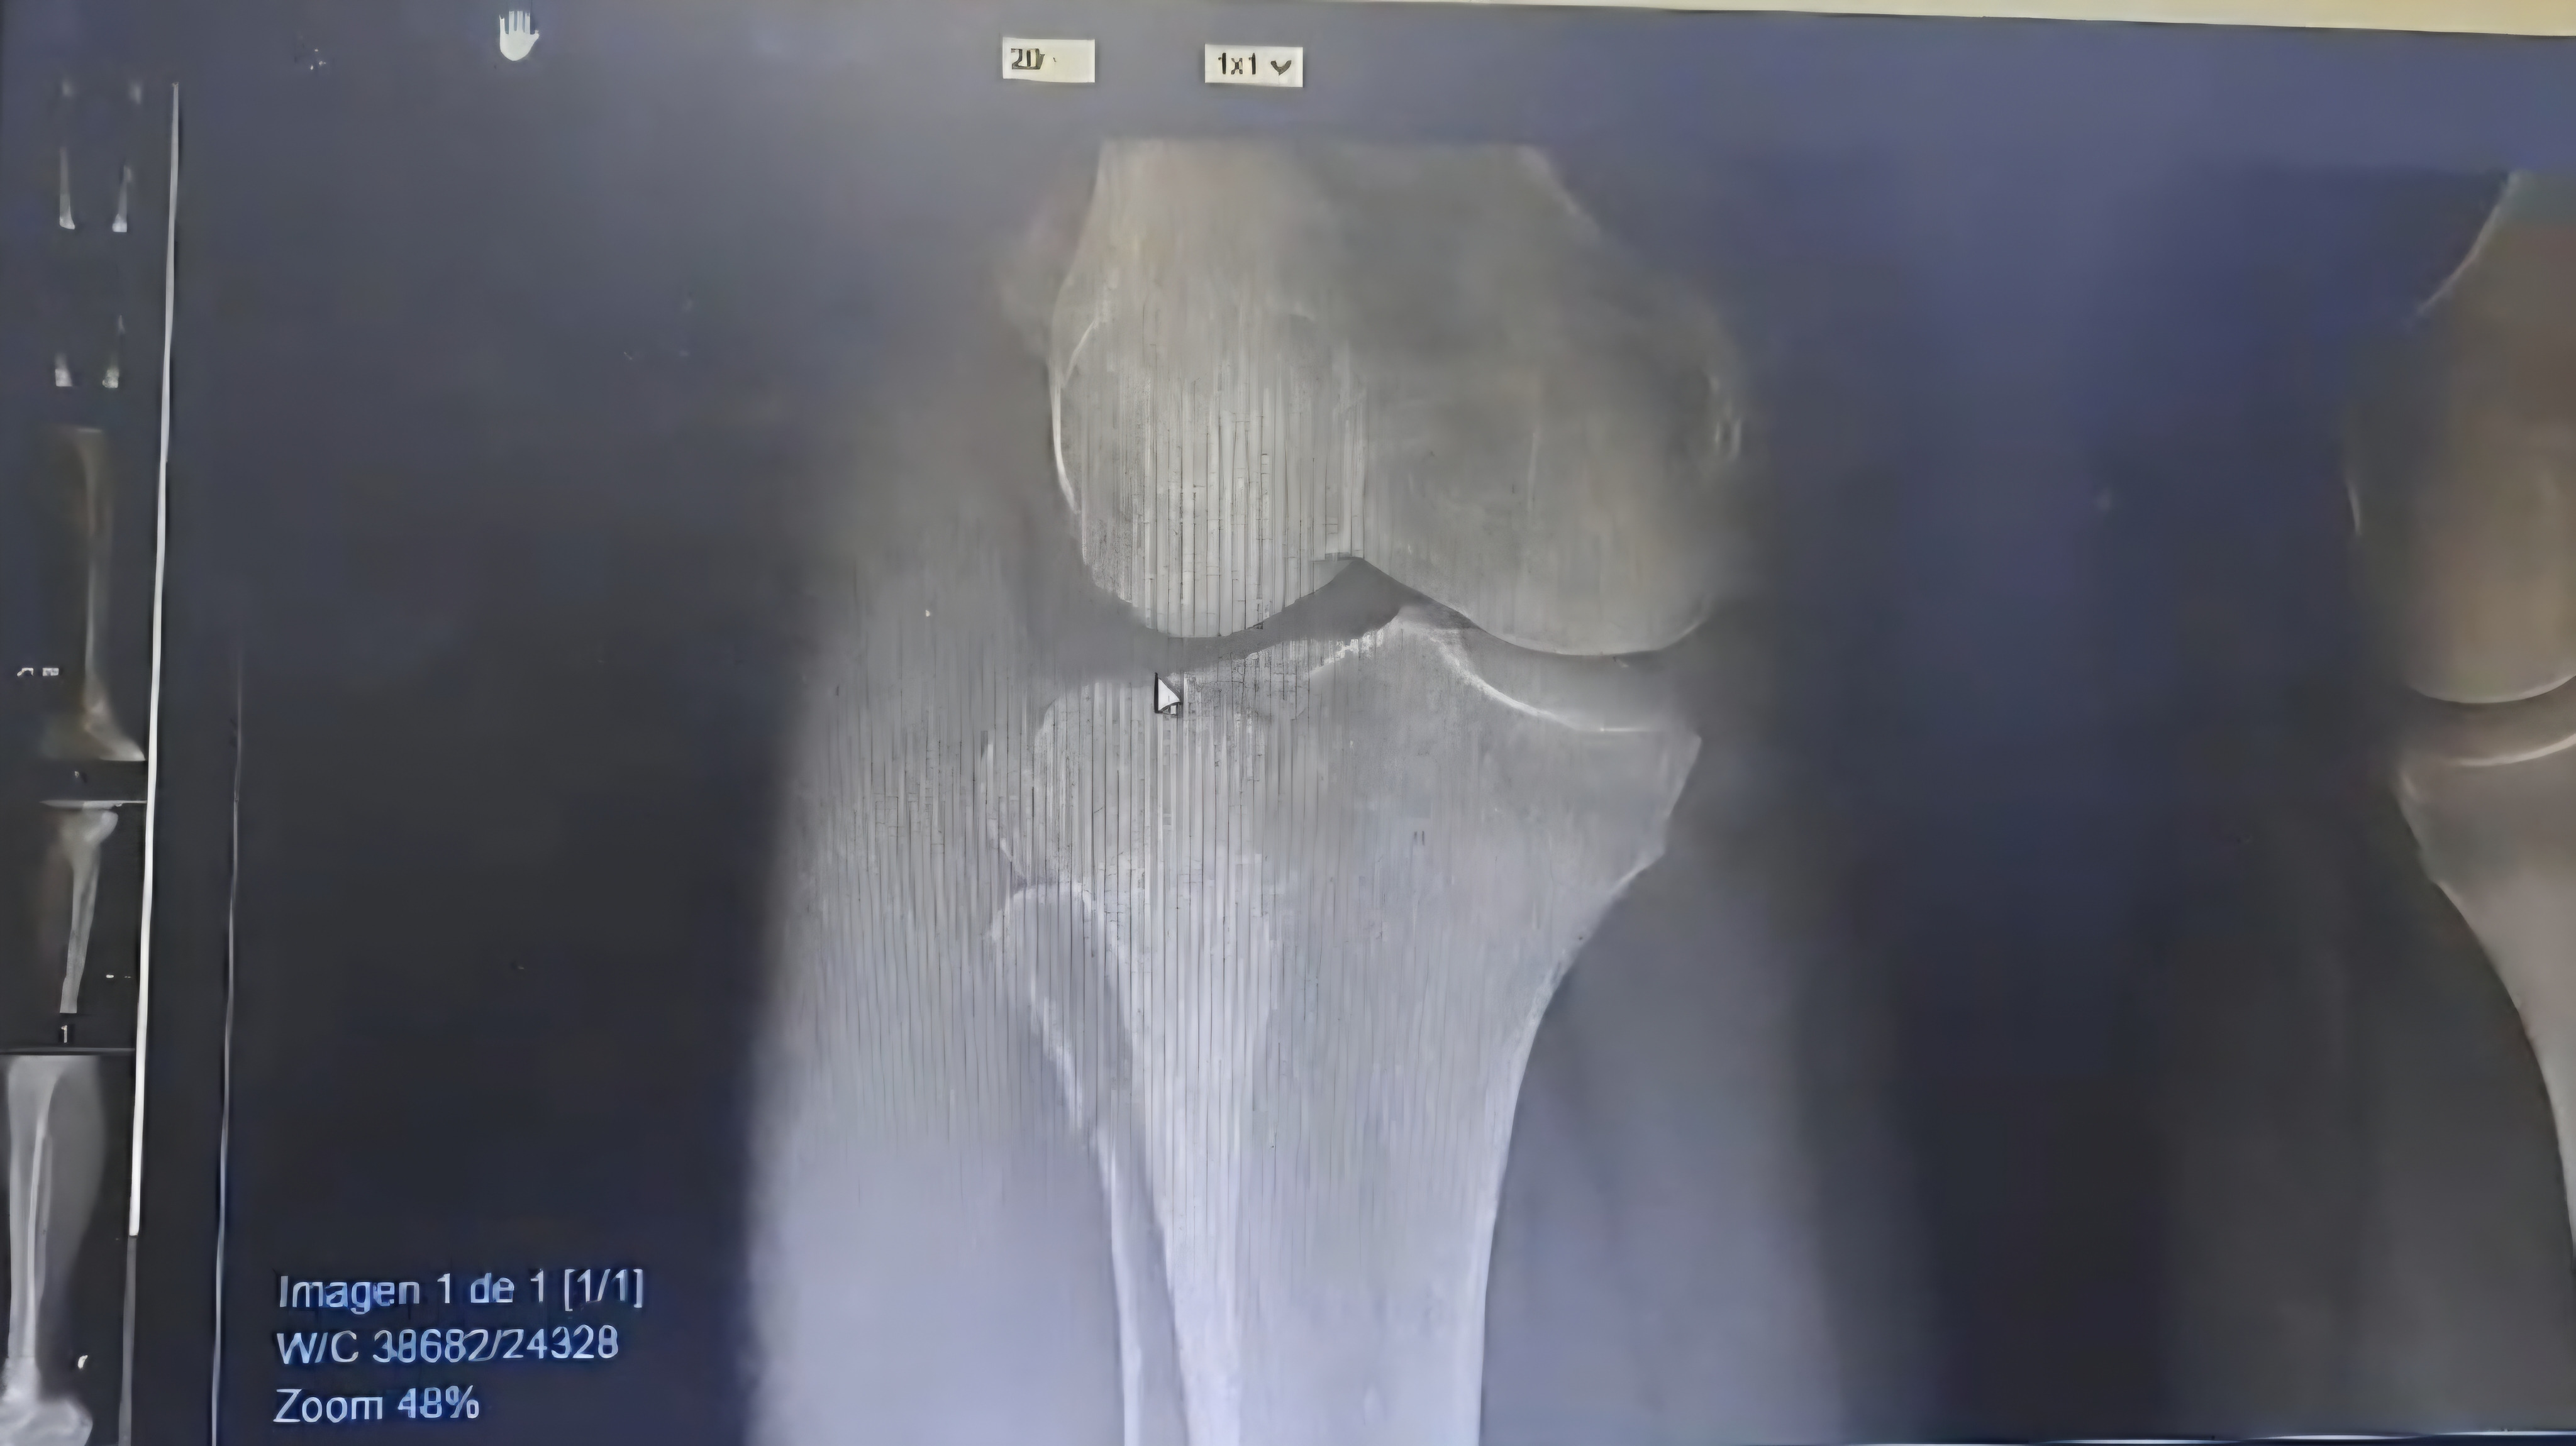

On Saturday, December 12th, my mother, Silvia Tucker de Rivera, was hit by a car while crossing an street on her way back to her home. She was immediately taken to the Santa Paula Medical Group in Caracas and hospitalized. She has multiple fractures, including a broken collarbone, three ribs, pelvis, and knee. She will undergo surgery to correct these fractures and will then face a long and undoubtedly expensive recovery, requiring rehabilitation and 24/7 care for quite some time.

El sábado, 12 de diciembre mi mama, Silvia Tucker de Rivera, fue atropellada por un automóvil mientras cruzaba un calle para regresar a su casa y enseguida fue trasladada y hospitalizada en el Grupo Medico Santa Paula en Caracas, tiene múltiples fracturas, entre ellas: clavícula, tres costillas, pelvis y rodilla, motivo por el cual será sometida a una operación para corregir sus fracturas y luego enfrentará una recuperación larga y claramente costosa por lo que necesitará rehabilitación y ayuda 24/7 durante un buen tiempo.